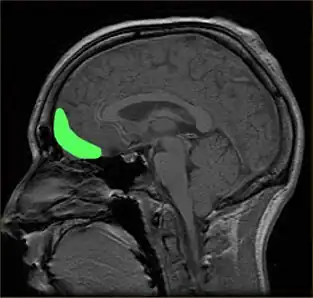

Approximate location of the OFC shown on a sagittal MRI | |